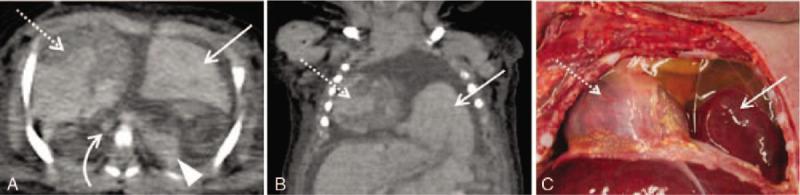

日本一家三级护理医院中,非增强型尸检计算机断层扫描在3岁及以下儿童院内非创伤性死亡调查中的应用

Utility of unenhanced postmortem computed tomography for investigation of in-hospital nontraumatic death in children up to 3 years of age at a single Japanese tertiary care hospital.

To evaluate the utility of unenhanced postmortem computed tomography (PMCT) for the investigation of in-hospital nontraumatic death in children up to 3 years of age.This study included the cadavers of children who died from intrinsic diseases before 3 years of age. The major underlying disease and the main organ-disease systems associated with the immediate causes of death were determined by clinical evaluation, PMCT, and autopsy, which were used as a reference standard. The rates of concordance between the former two methods and autopsy were calculated for all cases.In total, 22 cadavers (12 male and 10 female; mean age, 6.1 ± 8.2 months) were included. The rates of concordance between clinical evaluation/PMCT and autopsy for diagnosis of the major underlying disease and main organ-disease systems associated with the immediate causes of death were 100%/36% (P = .0015) and 59%/41% (P = .37), respectively. In cases where the respiratory system was associated with the immediate cause of death, PMCT showed greater diagnostic sensitivity (90%) than did clinical evaluation (20%). In contrast, the diagnostic sensitivity of PMCT was lower than that of clinical evaluation in cases involving disorders of the cardiac system and multiple organ systems (0% vs 100% for both).The findings of this study suggest that the use of unenhanced PMCT with clinical evaluation can result in improved detection of the immediate cause of death in select cases of in-hospital nontraumatic death before 3 years of age.

摘要

评估非增强型尸检计算机断层扫描(PMCT)在调查3岁以下儿童院内非创伤性死亡中的应用价值。本研究纳入了3岁前因内在疾病死亡的儿童尸体。通过临床评估、PMCT和作为参考标准的尸检来确定主要潜在疾病以及与直接死因相关的主要器官疾病系统。计算前两种方法与尸检在所有病例中的一致性率。总共纳入了22具尸体(12例男性和10例女性;平均年龄6.1±8.2个月)。临床评估/PMCT与尸检在诊断主要潜在疾病以及与直接死因相关的主要器官疾病系统方面的一致性率分别为100%/36%(P = 0.0015)和59%/41%(P = 0.37)。在呼吸系统与直接死因相关的病例中,PMCT显示出比临床评估更高的诊断敏感性(90%对20%)。相比之下,在涉及心脏系统和多器官系统疾病的病例中,PMCT的诊断敏感性低于临床评估(两者均为0%对100%)。本研究结果表明,在3岁以下儿童院内非创伤性死亡的特定病例中,结合临床评估使用非增强型PMCT可提高对直接死因的检测。